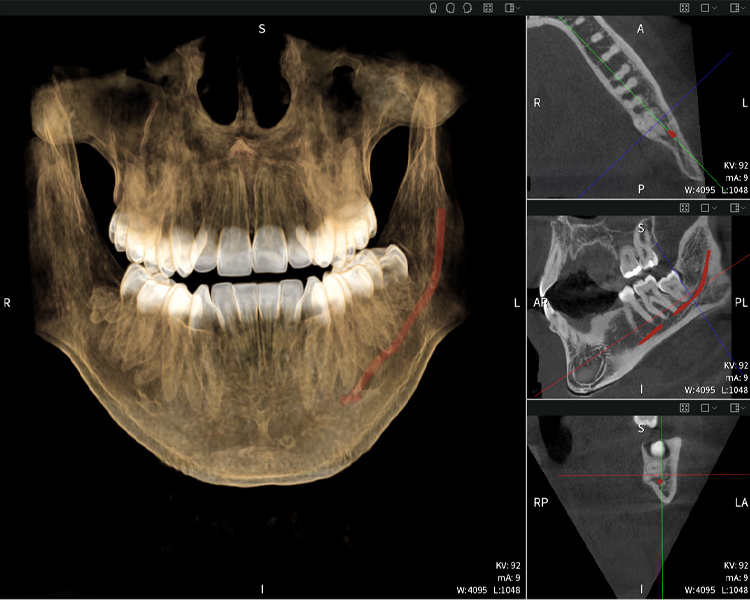

Figures b–d show various views of a 3D reconstruction of the mandible, providing a comprehensive overview of the mandibular anatomy, the position of the nerves in relation to the teeth, and allowing assessment of tooth symmetry and alignment.